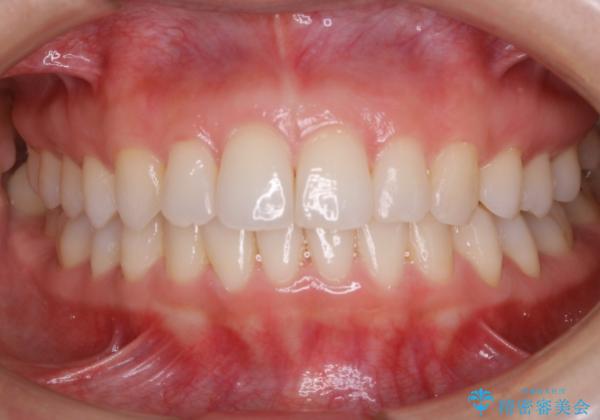

【非抜歯】前歯のガタつき マウスピースの部分矯正

- 上下の前歯の細かいガタつきの治療をご希望されて来院されました。

奥歯部分にはガタつきや噛み合わせの問題などがほとんど見られず、前歯のガタつきも軽度だったため、インビザライン ライト パッケージでの部分矯正を行うこととなりました。

今回のケースでは奥歯の噛み合わせに問題がほぼみられなかったため、前歯の位置のみに焦点を当て部分矯正を行いました。

適応されるケースが限られるものの、適応であった場合の治療期間は全体矯正と比べると格段に短くなり、費用も抑えられます。